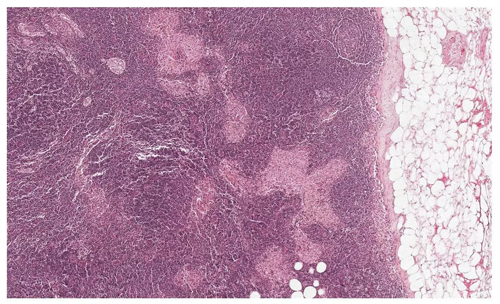

▲你能從這張切片中,找到哪些是腫瘤,哪些是正常組織,哪些是看起來很像腫瘤的正常組織嗎?(圖片來源:谷歌)

許多疾病的診斷依賴于病理學家對于組織切片的分析,這也成為了疾病診斷的黃金標準。對乳腺癌患者來說,病理學家將用顯微鏡鏡檢的方法,仔細觀看乳腺旁的淋巴結,尋找腫瘤的痕跡。根據鏡檢的結果,病理學家將告訴患者乳腺癌所處的階段,以及腫瘤是否發(fā)生轉移。這些分析直接決定了患者要采取的治療手段與疾病管理方法。據估計,全美每年有23萬乳腺癌患者需要接受這樣的診斷,聆聽醫(yī)生對她們命運的宣判。